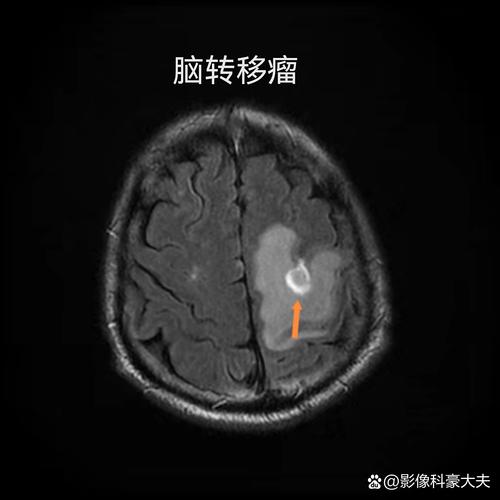

(图片来源网络,侵删)